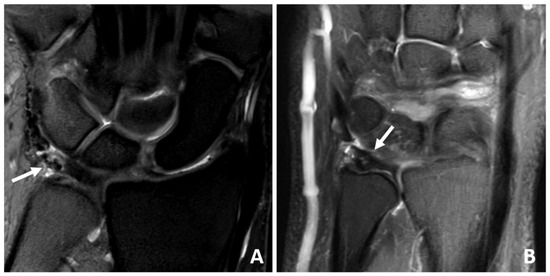

2.5. Magnet Resonance Imaging

3.4. MRI Scan